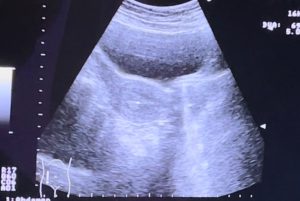

IUI – thụ tinh nhân tạo hay còn gọi là bơm tinh trùng vào buồng tử cung. Phương pháp điều trị này đơn giản và an toàn. Là phương pháp dùng một ống thông nhỏ, bên trong có chứa tinh trùng đã lọc rửa, chọn lọc, đưa qua cổ tử cung và bơm trực tiếp vào buồng tử cung người phụ nữ khi trứng đã trưởng thành. Quá trình thực hiện rất nhanh (khoảng 2-5 phút) và thường không gây đau đối với người bệnh.

Thời điểm thực hiện bơm tinh trùng vào buồng tử cung

Khi nào bệnh nhân được thực hiện bơm tinh trùng vào buồng tử cung?

- Sau khi tiêm mũi thuốc rụng trứng (hCG) 36-40 giờ.

- Tinh trùng của người chồng được lấy bằng cách thủ dâm. Sau đó được lọc rửa và bơm vào buồng tử cung bằng một ống nhỏ chuyên dụng.

- Chọn lọc những tinh trùng di động tốt để tăng khả năng thụ tinh với trứng.

- Loại được một phần chất kích thích co thắt tử cung trong tinh dịch.

- Loại được tế bào chết, vi sinh vật có hại cho tinh trùng.

- Thể tích tinh trùng sau khi lọc rửa và cô đặc là 0.2 – 0.3 ml. Nếu nhiều hơn, tinh trùng sẽ có khả năng chảy ngược ra ngoài sau khi bơm.